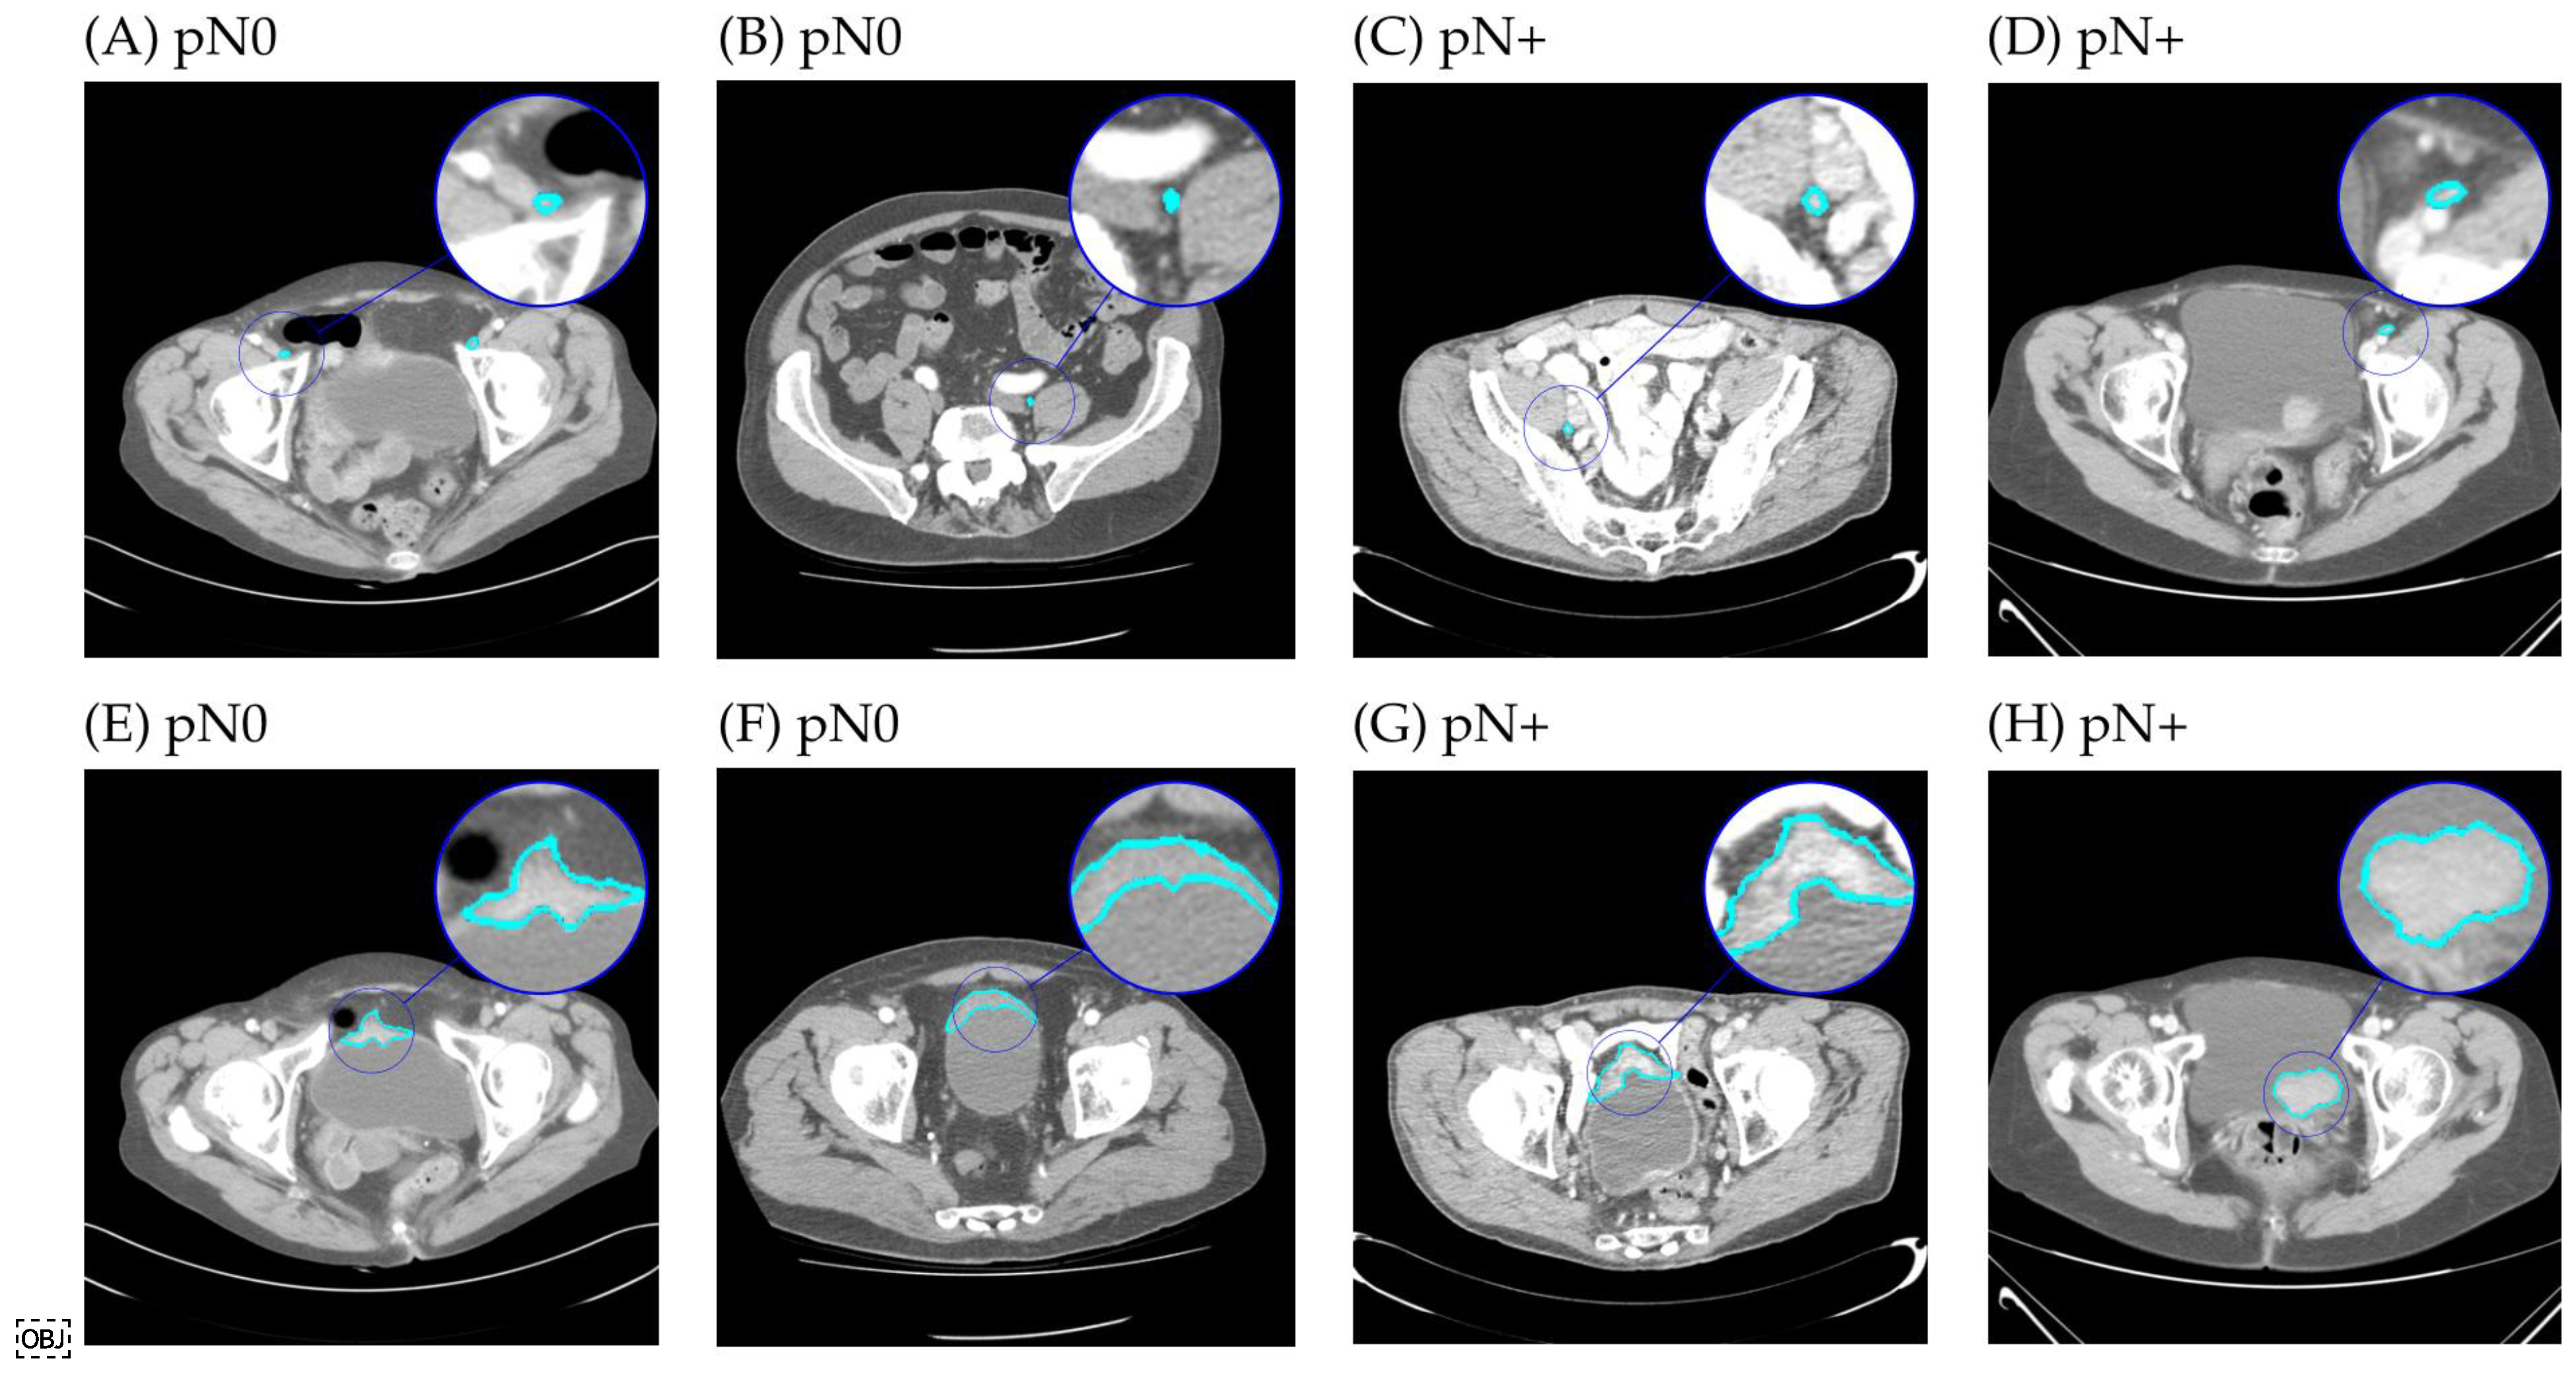

2.4. Segmentation